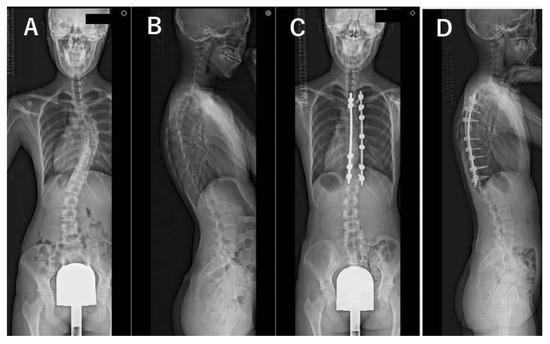

2. Materials and Methods

3. Results

3.3. Radiographic Evaluations